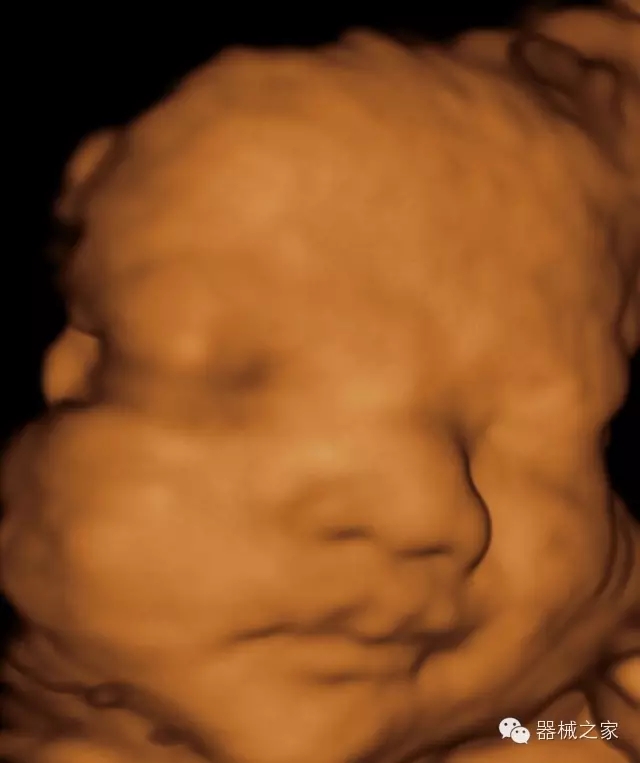

經(jīng)典產(chǎn)品:VINNO 6

臨床圖片賞析

產(chǎn)品特點

·獨(dú)有的RF平臺提高微小細(xì)節(jié)顯示、圖像對比度和邊界清晰度;

·特有的XCEN探頭,超寬的帶寬,表現(xiàn)更高分辨率和對比度;

·單晶純凈波探頭提供更佳的穿透力和彩色敏感度;

·完整的3D/4D臨床應(yīng)用,STIC, MCUT 和Auto NT等滿足產(chǎn)科所有應(yīng)用;

·更高的HQ羊膜腔鏡成像技術(shù)精細(xì)觀察每一個暗區(qū)細(xì)節(jié);

·智能的觸摸屏界面,能任意角度方位旋轉(zhuǎn)3D圖像,以及注釋快速標(biāo)記,提供直觀與便捷的操作,提高了工作效率;

介入室/手術(shù)室

·Needle Enhancement 穿刺增強(qiáng)技術(shù),清晰顯示穿刺針尖,定位目標(biāo)精確穿刺;

·智能的聲控功能,以及全屏顯示真正意義上解決醫(yī)生術(shù)中應(yīng)用;

Xcen探頭技術(shù)

·獨(dú)有的Xcen高頻18MHz探頭,使微小病灶的顯示成為現(xiàn)實,為臨床提供了更廣泛的臨床應(yīng)用;

·Xcen超寬頻帶探頭技術(shù)比常規(guī)探頭頻寬提高了30%,具有更廣泛的臨床應(yīng)用,更高的頻率讓我們獲得了更好的細(xì)微分辨率和對比度的圖像;

肌骨理療

·智能感知組織特異性的VTissue技術(shù),結(jié)合特有高達(dá)22MHzXcen線陣探頭, 以及獨(dú)有敏感的RF射頻血流提供了優(yōu)異臨床圖像;

·智能的教學(xué)操作流程提供全面及專業(yè)的操作步驟指導(dǎo),便捷藍(lán)牙傳輸保障信息流暢;

便捷傳輸功能

·藍(lán)牙傳輸/ WIFI 郵件/ 移動網(wǎng)絡(luò)/ DICOM;

·ICU/CCU;

·飛依諾特有心臟純凈波探頭提供更好的穿透力和彩色敏感度,以及結(jié)合TView梯形拓展改善困難病人深部組織成像;

·獨(dú)有RF敏感血流使得心臟血流完美呈現(xiàn);

CFDA注冊證編號

·國械注準(zhǔn)20152231021